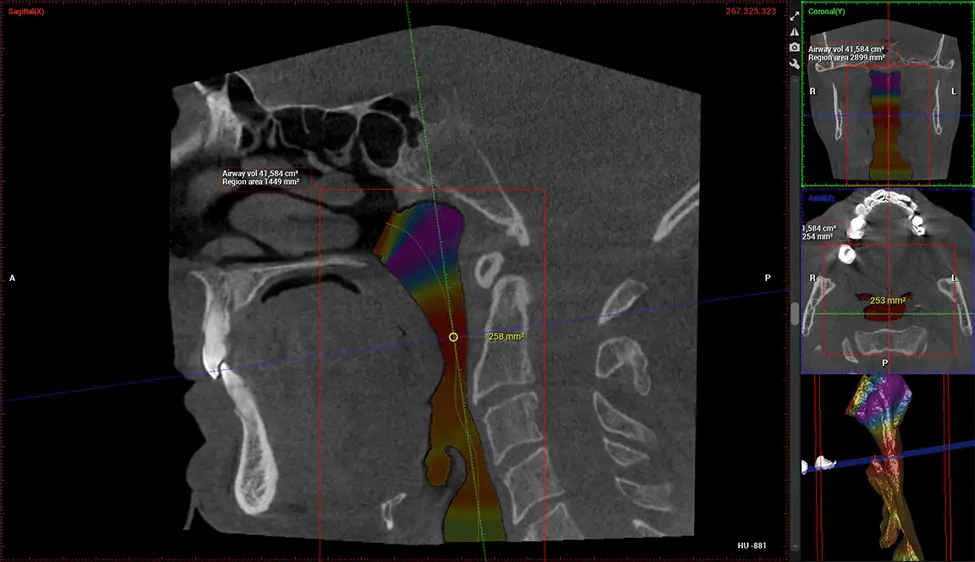

ENT Physician Diagnosing obstructive sleep apnea (OSA) and evaluating sinus and nasal cavity anatomy. Visualizes the entire pharyngeal airway to measure volume, pinpoint constrictions, and plan corrective surgery if needed.

Screening and treating patients at risk for OSA.

Provides detailed 3D imaging for airway analysis, helping to create and adjust oral appliances and facilitate effective referrals to medical doctors.

Orthodontist Assessing facial asymmetry, planning orthognathic surgery, and managing cleft lip and palate and sleep apnea. Provides a comprehensive view of the craniofacial complex to better plan treatments and evaluate outcomes.